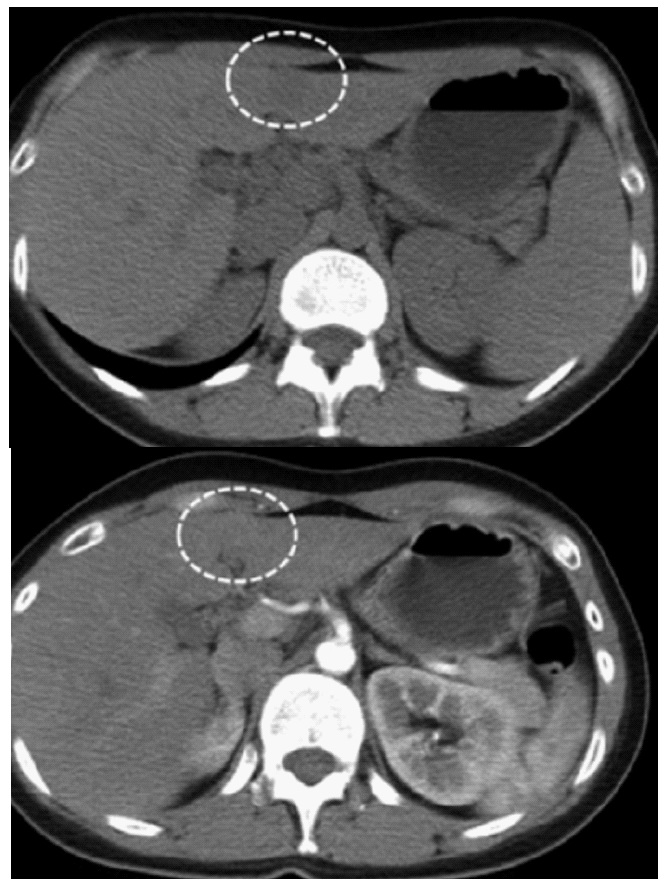

The CT scanner revealed a 2.7 cm hypodense tumor in left lateral segment, with hyperenhancement in arterial phase and wash-out in veinous phase (Figure 1). He was diagnosed with hepatocellular carcinoma and underwent laparoscopic left lateral segmentectomy. The tumor was located in the central of segment 3. The spicimen was shown in (Figure 2). The postoperative course was uneventful, and the patient was discharged on postoperative day 5.

Figure 1: The CT’s images of the liver tumor pre-operation.